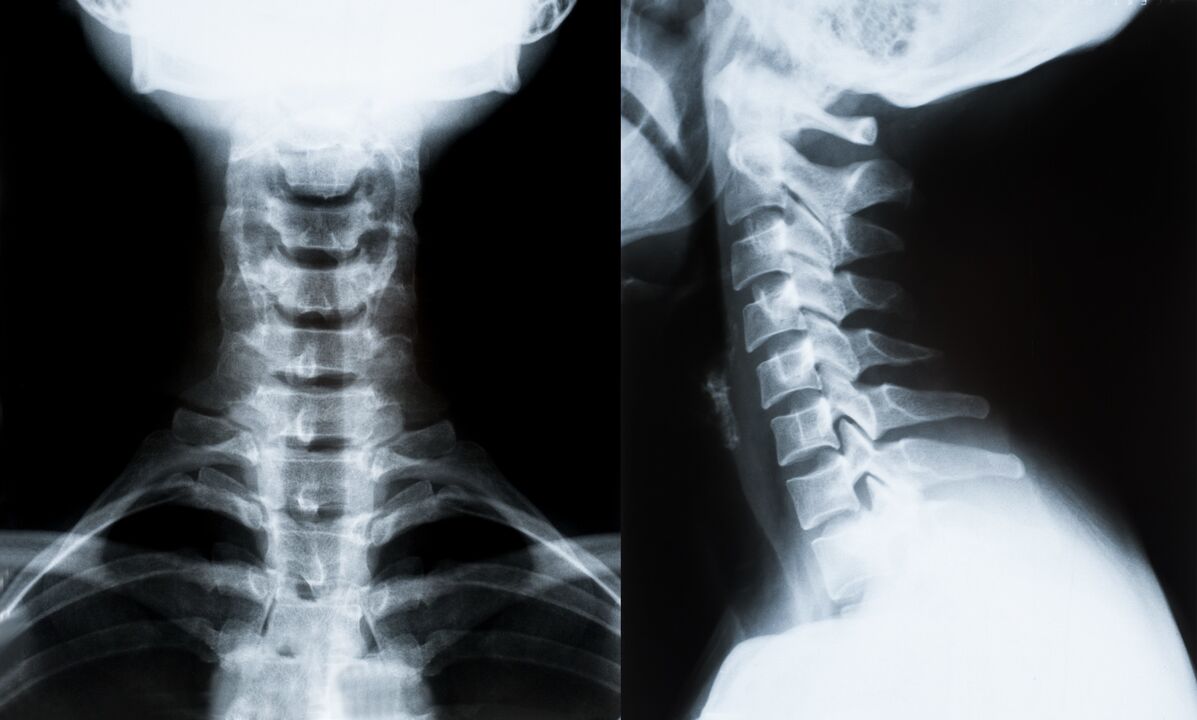

Os principais métodos de diagnóstico e posterior determinação do tratamento da osteocondrose da coluna cervical:

- Raio X. O método de diagnóstico menos eficaz, mas tradicional.

- A ressonância magnética é o método diagnóstico mais eficaz. Com esse tipo de exame do paciente, todas as estruturas necessárias ficam visíveis.

- Se for necessário medir alterações, a tomografia computadorizada é usada. Determina a presença de hérnias e outras coisas.

- O último método é a varredura duplex por ultrassom. Este método de pesquisa determina a velocidade do fluxo sanguíneo nas artérias.

É impossível determinar com precisão a doença da coluna vertebral em casa.